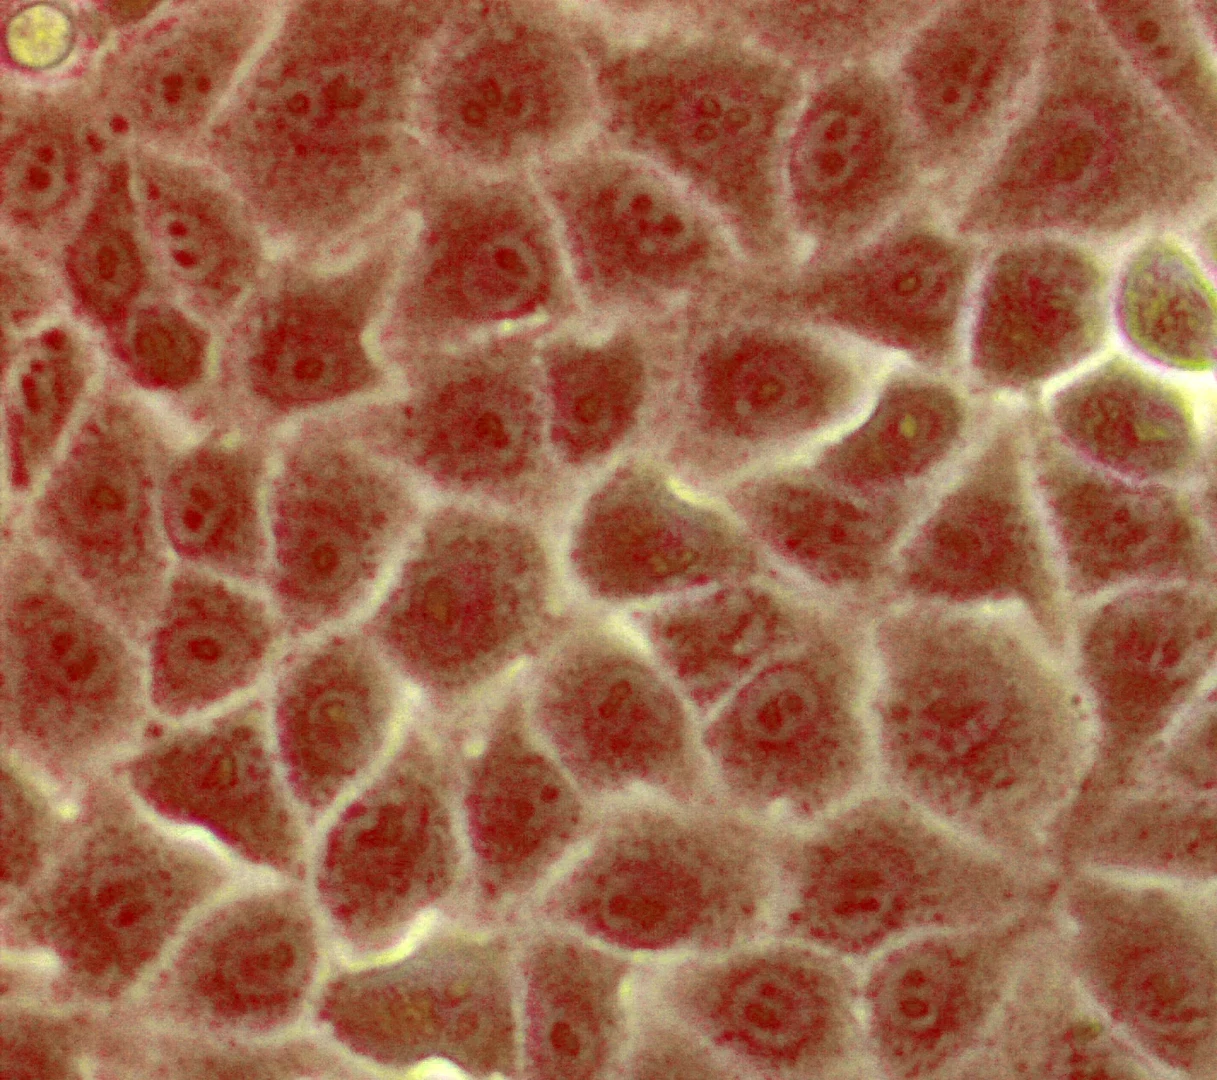

Nierenepithelzellen

Nierenepithelzellen - von der Zwergfledermaus (Pipistrellus pipistrellus). Die Wissenschaftler zeigten an diesen Zellen, dass auch das Fledermaus-DPP4 als Rezeptor für das HCoV-EMC/2012 funktioniert. Rot ist der Zellkern mit der DNA zu erkennen, weiß sind die Zellgrenzen. © Foto: Marcel Müller/Uni Bonn